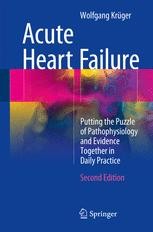

61QhzyaN0mL._AC_UF1000,, Methods in Treating Heart Failure - Device and Surgery,

Methods in Treating Heart Failure - Device and Surgery, Acute Heart Failure: Putting the Puzzle of Pathophysiology,

Acute Heart Failure: Putting the Puzzle of Pathophysiology, Back to Basics: Heart failure medication - Issues and Answers,

Back to Basics: Heart failure medication - Issues and Answers, CONGESTIVE HEART FAILURE: THE ULTIMATE GUIDE TO,